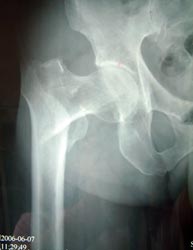

患者82岁,男性,股骨粗隆间粉碎骨折,伴有冠心病、骨质疏松。

采用小切口微创双极人工股骨头置换术置换术,骨折块用钢丝固定。

术后5天下地活动,恢复满意。